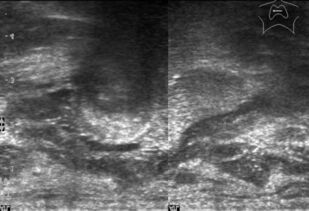

В основу монографии положены материалы собственных исследований и практический опыт использования ультразвуковых методов диагностики при обследовании пациентов после хирургических вмешательств на щитовидной железе. Продемонстрированы диагностические возможности ультразвукового исследования в оценке состояния оперированной щитовидной железы в раннем и отдаленном послеоперационном периоде. Обобщена, систематизирована и представлена ультразвуковая семиотика зоны операции в ближайшие сроки после хирургических вмешательств и отражена динамика выявленных изменений. Убедительно показано, что ультразвуковое исследование может быть эффективным методом послеоперационного наблюдения.